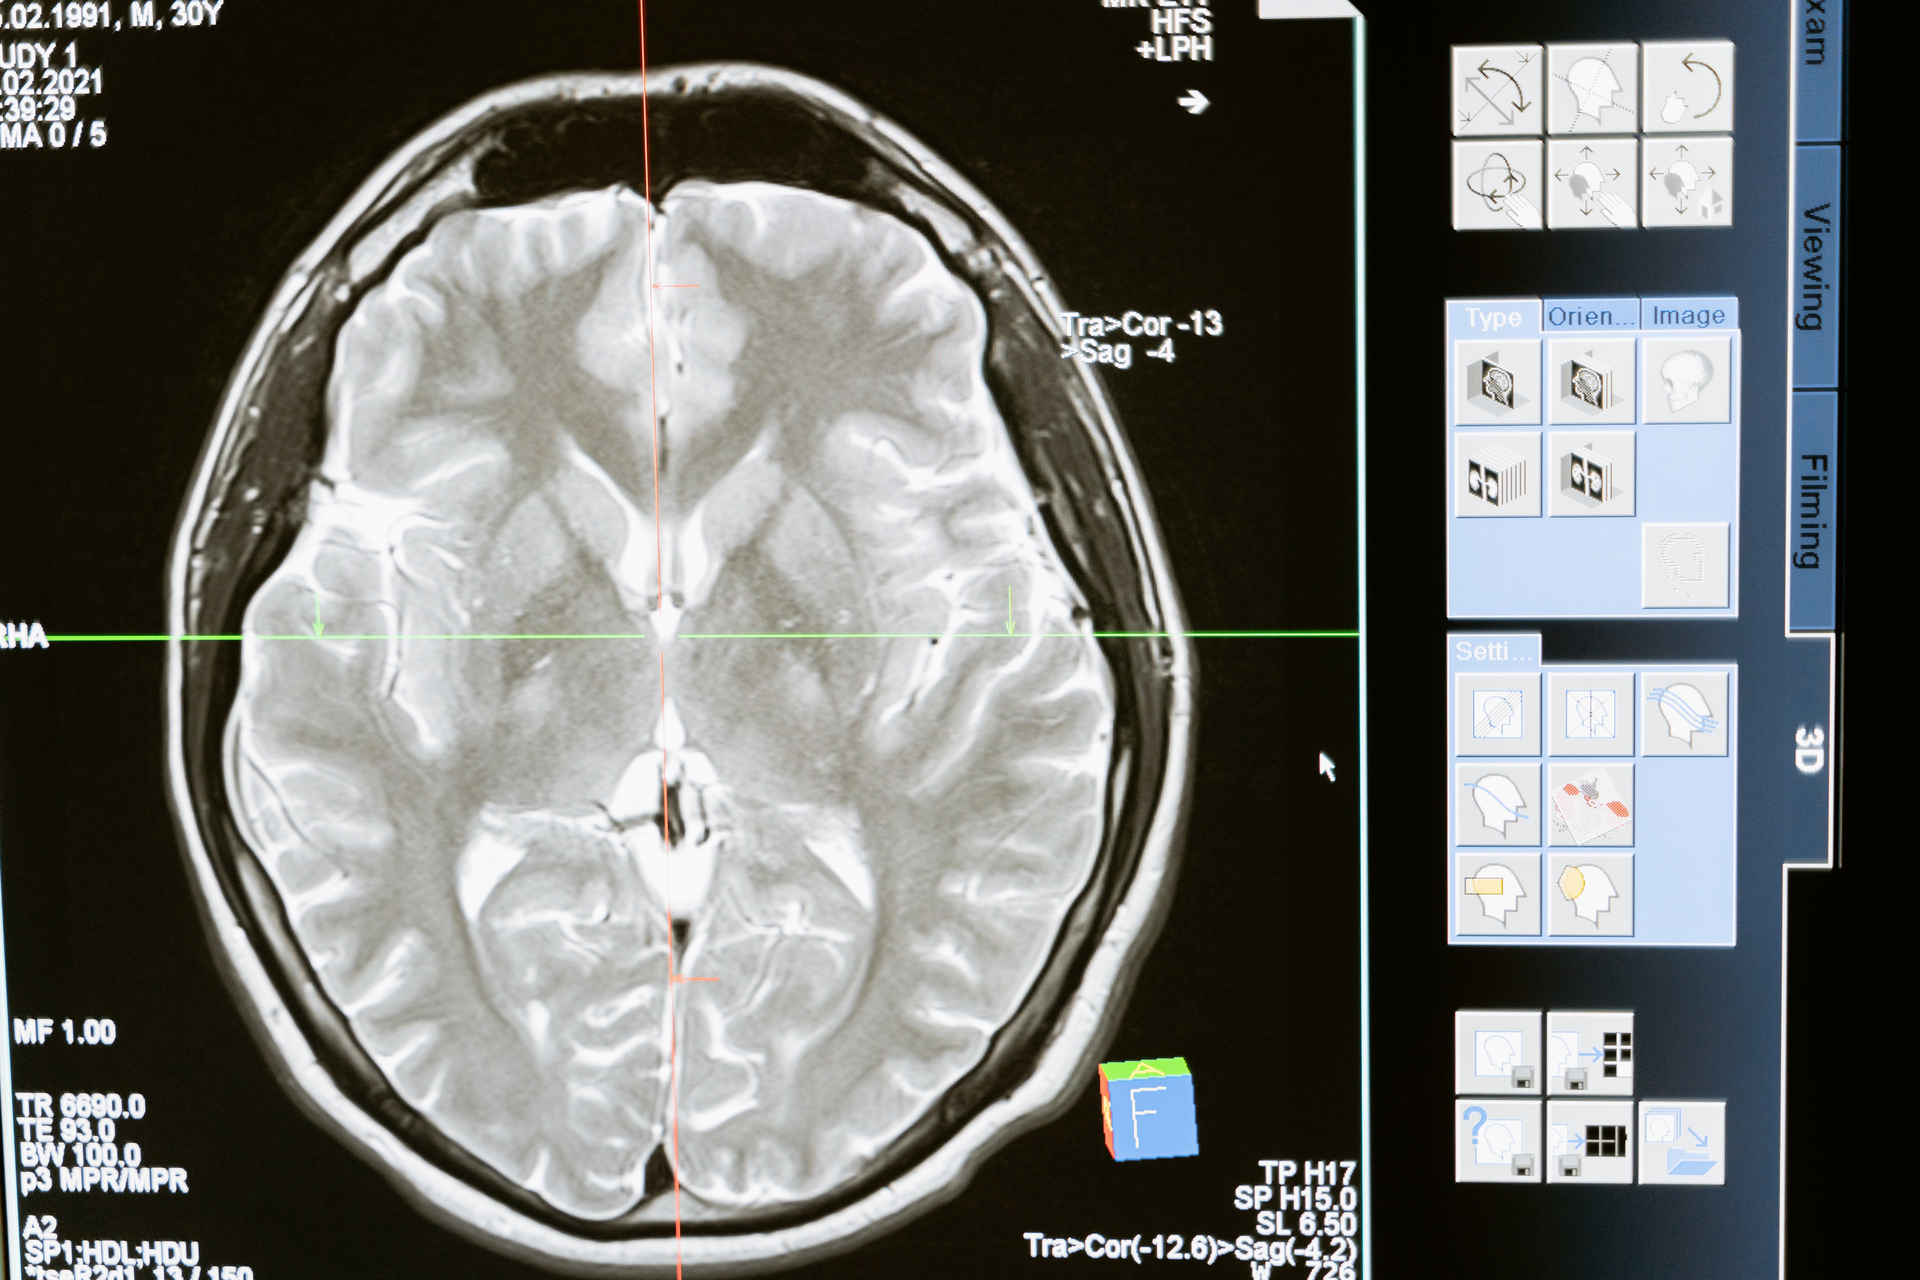

In a small study, researchers funded by the National Institutes of Health captured more than 1,000 hours of brain recordings from patients with OCD in the clinic and at home. These data are a key first step towards designing improved deep brain stimulation (DBS) treatments for neuropsychiatric disorders.

In the current study, brain recordings were taken from the same electrodes responsible for delivering the DBS therapy and time-synched to EEG, other physiological recordings, and facial changes when recorded in the clinic; to efforts to evoke symptom responses during teletherapy sessions; and to self-reported symptoms during everyday life and during prescribed tasks at home.

By combining these diverse data sets, the researchers were able to begin identifying candidate neurological signatures for OCD, such as brain activity changes that occurred over time in correlation with clinical scores for OCD symptoms. Going forward, the researchers plan to tweak the stimulation in response to the candidate biomarkers to confirm whether they can be used to impact the onset of symptoms.